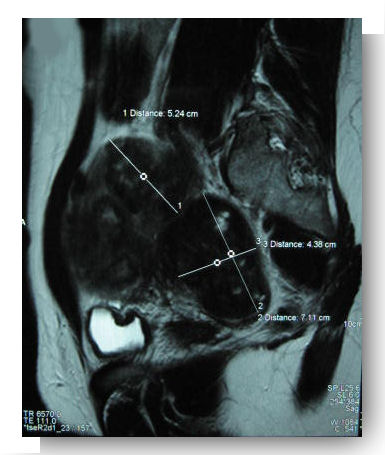

- IRM pelvienne : Une imagerie par résonance magnétique permet de compléter le bilan en cas de doute diagnostique (fibrosarcome utérin) et d’établir une cartographie utérine en cas de fibromes multiples.